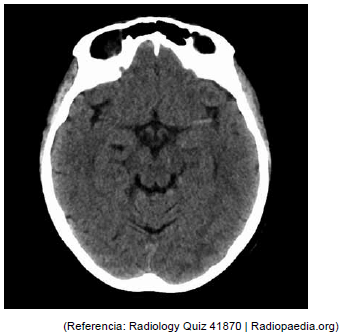

ACO, 70 anos, com antecedente prévio de hipertensão arterial e cardiomiopatia chagásica. Levada por familiares ao pronto-socorro, relatando que ela foi dormir bem por volta de meia noite no dia anterior e hoje, de madrugada, encontraram-na arresponsiva. À admissão hospitalar às 5h30 da manhã, estava hipertensa, com pressão arterial de 181 x 100 mmHg; frequência cardíaca de 68 bpm, saturação em ar ambiente 82%, glicemia capilar de 81mg/dL. Para estabilização hemodinâmica, necessitou prosseguir com intubação orotraqueal, sedoanalgesia e monitorização. Eletrocardiograma em ritmo sinusal. Coletaram-se exames séricos e foi encaminhada ao setor de tomografia. Constatou-se a imagem a seguir. Qual o nome do sinal apresentado nessa tomografia de crânio?